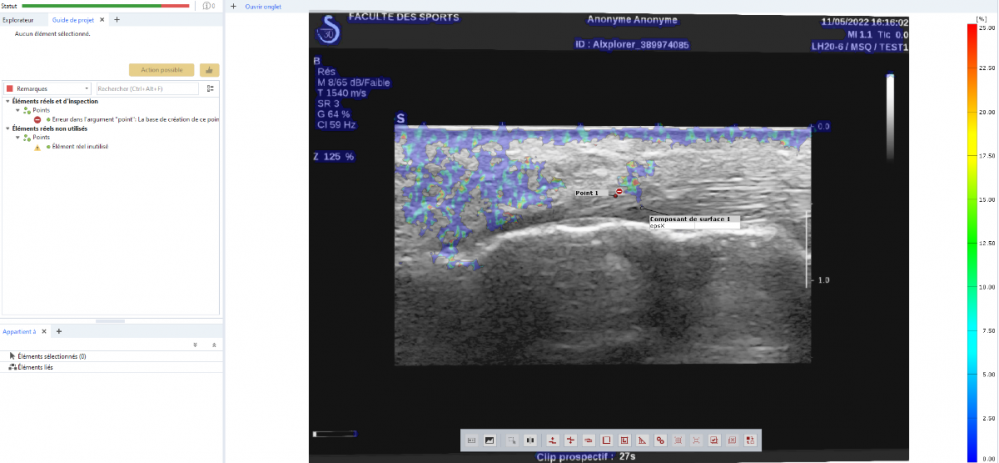

[Zo...] Posted June 17, 2022 Author Share Posted June 17, 2022 Here is a screenshot of the error I get at the end of the calculation. Link to comment Share on other sites More sharing options...

[Iv...] Posted June 20, 2022 Share Posted June 20, 2022 It seems that the SW can't create/find the point component anymore. Do you have any greater movement in between two stages of your point component? Do you have a rigid or deforming component? Can you make two screenshots? One in a stage were the component is found and one with the error? Check also in the creation parameter of your component (click F4, while the component is selected) and tell me the component type Link to comment Share on other sites More sharing options...

[Zo...] Posted June 20, 2022 Author Share Posted June 20, 2022 This is an ultrasound video of a tendon at the point where it hooks onto the bone. My goal is to get the deformations at the interface tendon/bone. It is a deformable component which evolves in a deformable environment since the whole of the video (fat, bone) moves because of the movement. The component type is surface component (calculation option : get more points) as it is a 2D video. Link to comment Share on other sites More sharing options...

[Zo...] Posted June 20, 2022 Author Share Posted June 20, 2022 I made here the calculation on the whole video because by selecting only the part of interest the calculation does not work at all Link to comment Share on other sites More sharing options...

[Iv...] Posted June 21, 2022 Share Posted June 21, 2022 Thanks Zoe, the screenshots are very helpful. The main problem is that your surface is not as good as it should be for a deformation analysis. Especially the grayvalue distribution. The point you created is based on the surface component. If you lose your surface component you lose your point. This is the error you see in your screenshot. If would recommend, if you like to inspect a discrete point, to create a facet point. There you use a facet to create and find a specific point. Link to comment Share on other sites More sharing options...